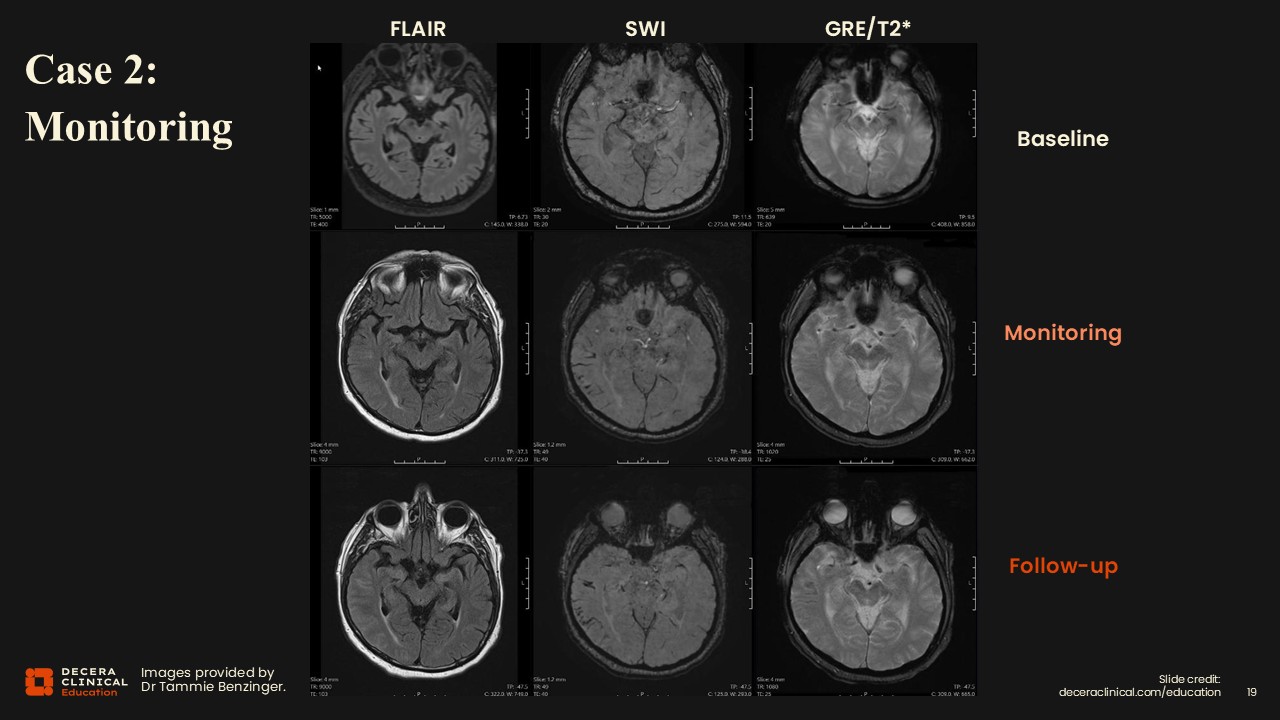

After ATT was initiated, monitoring MRI revealed new FLAIR hyperintensity involving a single, relatively large region (>9 cm) with sulcal effacement and subtle sulcal effusions, consistent with ARIA-E.

In the same region, SWI demonstrated signal loss compatible with superficial siderosis. Without careful comparison to the prior study, these findings could easily be overlooked.

Regarding ARIA classification, we have a single region measuring over 9 cm on FLAIR, and upon careful inspection, effacement of the sulci and even some small sulcal effusions can be seen. In those same ARIA regions that have the sulcal effusions, there is a loss of signal on susceptibility, indicating a little bit of siderosis starting. The FLAIR abnormality is classified as moderate because it is less than 10 cm. However, 3 areas of siderosis place this in the severe ARIA-H category.